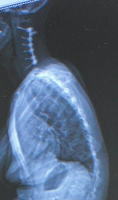

XX病院受診 EOSにて全身の様子を見てくださる 前と同じ状態との事で、頸椎も異常なしで、次は半年後 ![]() これが、EOSの画像です 首のボルト画像が、よくわかります 背中の画像で、圧迫骨折の為に、まるくなっているのも解ります ![]() こちらは、ちょと驚きです 背中の丸みが、身体の均衡迄崩しています 左肩が下がっているとか ちょっと見苦しい写真ですね 左側に足を崩す癖があったから、こうなったのかもしれません 一種の背骨湾曲症だそうです 足の方まで続くのですが、これ以上見苦しいのは、お見せ出来ないので切りました (注)EOSとは、一瞬にして、2方向同時に全身を撮ることができる 放射線量も低い放射線機器(この説明で良いと思いますが) |